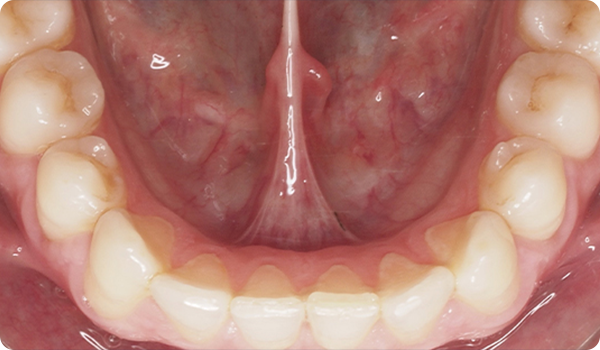

De praktijk stuurt drie foto's en het STL-bestand van een scan via Corus Link om de casus te beoordelen.